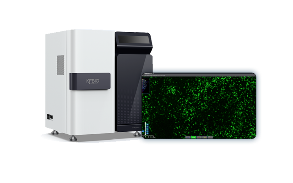

Digital Pathology Slide Scanner (PRO)

Digital Pathology Slide Scanner (PRO)

Fluorescence Scanning Features

KFBIO Digital Pathology Slide Scanners (fluorescence) have excellent performance in the accuracy of movement, focus, and image processing, and its accurate whole slide imaging not only meets the requirements of digital slide viewing and operation but is also suitable for AI-assisted image analysis.

Excellent Cross Color Suppression Design

Independent LED light source avoids cross color. High contrast, high brightness, no drift, and no cross color make it more suitable for specific fluorescence channels. Equipped with CHROMA filter narrowband filter, the minimum spectral band resolution reaches 10nm, which can efficiently separates different fluorescence channels to achieve large information density without affecting the quality of data.

High-Sensitivity Cooled Scientific CMOS Camera

Dhyana 400D high-sensitivity refrigeration scientific CMOS camera is equipped, low signal-to-noise ratio and high resolution, with a new 1.2 inch surface array scientific CMOS chip. The quantum efficiency at 600 nm is up to 80%. 6.5 μm pixel size and 2*2 pixel binning function realized by FPGA, suitable for low-light detection and imaging. The Dhyana 400D has excellent performance, with only 2 electrons of readout noise. The browsing speed is up to 35 frames/s at 4 megapixels. And the data transmission speed is up to 5Gb/s to provide strong support for users’ work.

Large Field of View, Long Work Life

The 26.5mm field of view keeps the image flat, decreasing shooting and exposure time. The LED light source ensures more than 20,000 hours work, long-lasting and simple to maintain. Non-contact Hall switches are used to power the light source, and wireless charging technology is introduced to save wiring, which boosts system stability.